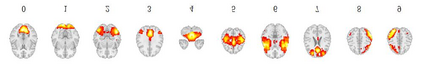

Using deep learning models to recognize functional brain networks (FBNs) in functional magnetic resonance imaging (fMRI) has been attracting increasing interest recently. However, most existing work focuses on detecting static FBNs from entire fMRI signals, such as correlation-based functional connectivity. Sliding-window is a widely used strategy to capture the dynamics of FBNs, but it is still limited in representing intrinsic functional interactive dynamics at each time step. And the number of FBNs usually need to be set manually. More over, due to the complexity of dynamic interactions in brain, traditional linear and shallow models are insufficient in identifying complex and spatially overlapped FBNs across each time step. In this paper, we propose a novel Spatial and Channel-wise Attention Autoencoder (SCAAE) for discovering FBNs dynamically. The core idea of SCAAE is to apply attention mechanism to FBNs construction. Specifically, we designed two attention modules: 1) spatial-wise attention (SA) module to discover FBNs in the spatial domain and 2) a channel-wise attention (CA) module to weigh the channels for selecting the FBNs automatically. We evaluated our approach on ADHD200 dataset and our results indicate that the proposed SCAAE method can effectively recover the dynamic changes of the FBNs at each fMRI time step, without using sliding windows. More importantly, our proposed hybrid attention modules (SA and CA) do not enforce assumptions of linearity and independence as previous methods, and thus provide a novel approach to better understanding dynamic functional brain networks.